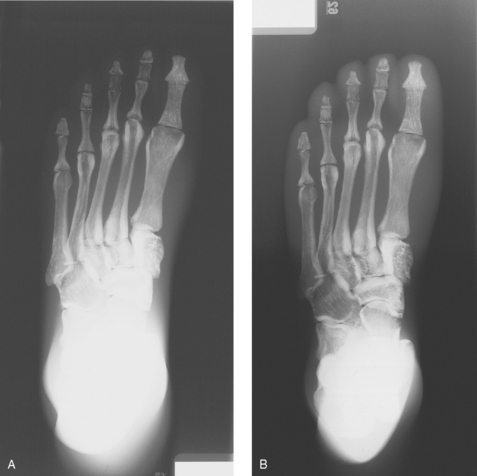

• Specialized wedge filters are designed for specific uses. Fig. 2-10 shows the results of using the Ferlic foot filter to provide a significantly improved image of the foot with one exposure.

Fig. 2-10 A, AP axial projection of foot. Note dark toe area and light tarsal area without filter. B, Same projection with use of Ferlic AP foot filter showing improved visualization of toes and tarsals.